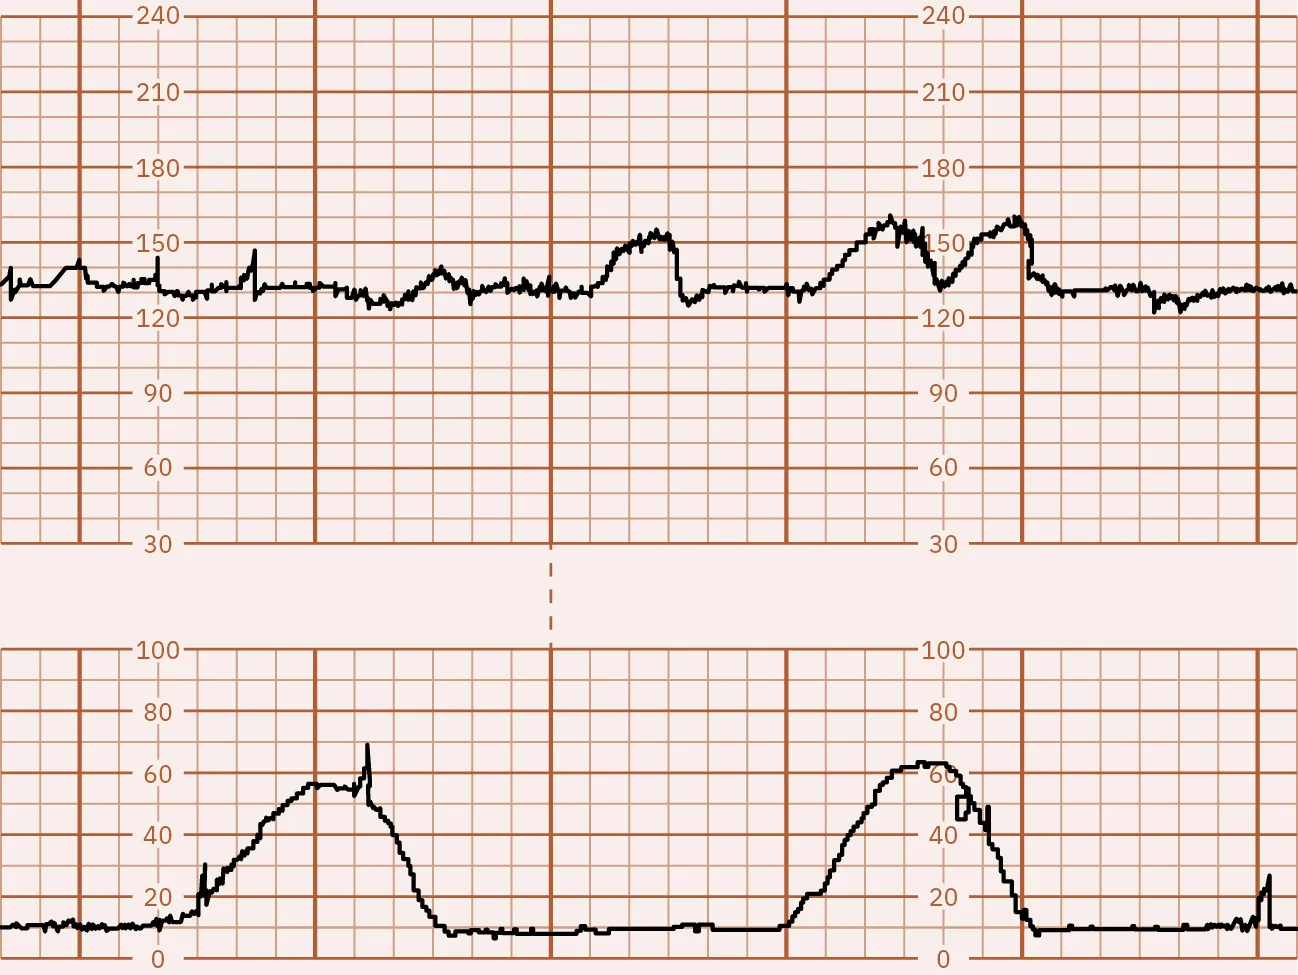

The CST test results are divided into several categories:

• Positive: Late decelerations occur after 50 percent or more of contractions, even if the contraction frequency is less than three in 10 minutes (Figure 13.12).

Fetal monitor tracing graphic depicting positive CST. Top strip displays dips in lines after second strip shows spikes.

Figure 13.12 Positive CST In this illustration, the FHR baseline is 130. The fetal heart rate is at the top and the contractions are on the bottom. This strip shows a dip in the fetal heart rate just after a contraction occurs, known as a late deceleration. (attribution: Copyright Rice University, OpenStax, under CC BY 4.0 license)